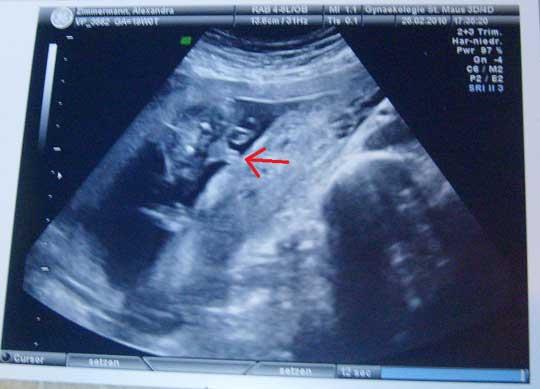

So...der 2. Große Ultraschall stand heute an. Der Arzt hat etwa eine halbe Stunde geschallt (Baby wollte nicht so mitspielen) und mal ganz ehrlich...also wenn hier iiiiirgendwer jeeeemals Angst haben sollte, dass mit dem Baby was passiert, wenn man mal einen Ellenbogen gegen den bauch kriegt, oder mal ne Schmusekatze draufspringt oder ein Geschwisterkind reinboxt...der war noch nie bei dem Arzt zum Ultraschall...man man...wenn das Kind nicht mitspielt, er aber unbedingt alle 4 Herklappen angucken will und den Blutfluss messen will...wahnsinn... Unser Kind ist völlig gesund und ach alle Hirn Ventrikel und Arterien und Herklappen und Löcher und sonstige Gefäße alles super und normal. Nabelschnur hat artig zwei Leitungen und die Gebärmutter wird ebenfalls gut versorgt. Rücken zu, Oberlippe geschlossen, alle Arm und Bein Knochen haben die Richtige Länge...yoah kurz und gut, das Kind ist Kerngesund. genaue Werte: US bei 19+0 BPD: 4,6 KU: 16,5 ATD: 4,5 AU: 14,0 FL: 2,8 ca. 300gramm schwer. Echo, AM, Doppler o.B. :) UND wir haben ein lt. Arzt 100%iges Outing. Weils so schön ist zeig ich euch erstmal nur das Beweisbild.

Herzlichen Glückwunsch. Ähm, soll es ein Mädel werden? Könnten die typischen 3 Striche sein, wenn ich mich nicht verguckt habe. LG Freya

Oder doch eher ein Junge? Je genauer ich es mir angucke desto unschlüssiger werde ich.

Ist ein Junge....die 3 Striche die du siehst, sind komplett die Penisspitze und dahinter die Hoden :)

darauf hätte ich auch Jung gesagt. So eindeutig ;-) Herzlichen Glückwunsch

Habe das Bild geöffnet und sofort "EIN JUNGE" gesagt. Noch deutlicher geht ja kaum!!!! Freue mich, dass mit dem Kleinen alles IO ist. Habt ihr schon einen Namen?